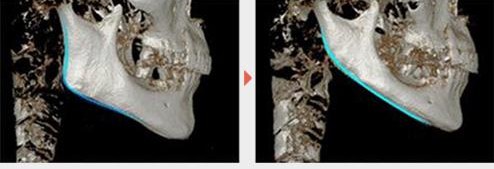

3、削下颌角

这样,下颌骨也可以从低角变成高角。而削骨的一个很大副作用就是下颌可能还会后旋。因为咬肌是附着在下颌骨下缘的。要想削下颌角,需要剥离咬肌。因此削骨也会造成一定的咬肌损失,使宽度从骨骼和肌肉两方面进行减小,方脸就会变成正常的脸型,甚至变成长脸。

下颌一旦出现后旋之后,颏部会更加不明显,会出现颏肌紧张这些症状怎么办?那就再垫下巴、或者颏部玻尿酸充填。这样进一步增加了面下三分之一的比例,就会更加破坏面部比例的协调。

我观察到的花花的面型变化应该就是这样,不管是那种原因导致的,花花从低角下颌后缩变成了高角下颌后缩,颏部更加不明显。因此采取了改善下巴颏的一些医美方式(垫下巴或者玻尿酸充填不详),这样就会显得颏部好看一些,没有那么紧张。但是延长了面下三分之一的长度,让我从直觉上感受到了面部的不和谐。

这个是最新病例,单纯正畸,没做手术,下巴出来了哦!(两张图耳朵不一样的原因是分别是左耳和右耳,两张照片拍照方向不一样,我做了一个镜面翻转)